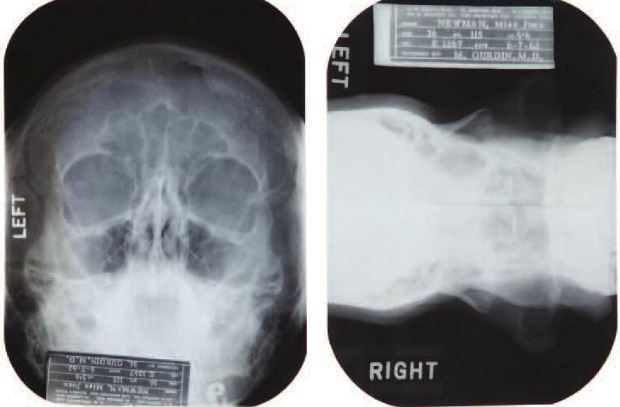

News broke last month that Marilyn Monroe had a little help from plastic surgery to help sculpt that iconically beautiful face of hers, and it was proven via medical records and X-rays that show the work she had done. As of yesterday, those very same records and X-rays sold at an auction in Hollywood for $25,600.

The X-rays and records were part of Julien’s Auctions’ “Icons and Idols: Hollywood” sale, and they cover Monroe’s private medical history from 1950 to 1962. During that time, she had a chin implant to correct what she perceived to be a “chin deformity,” as well as a “tip rhinoplasty” on her nose. A bit more morbidly, the records also detail Monroe’s painful recovery after experiencing an ectopic pregnancy.